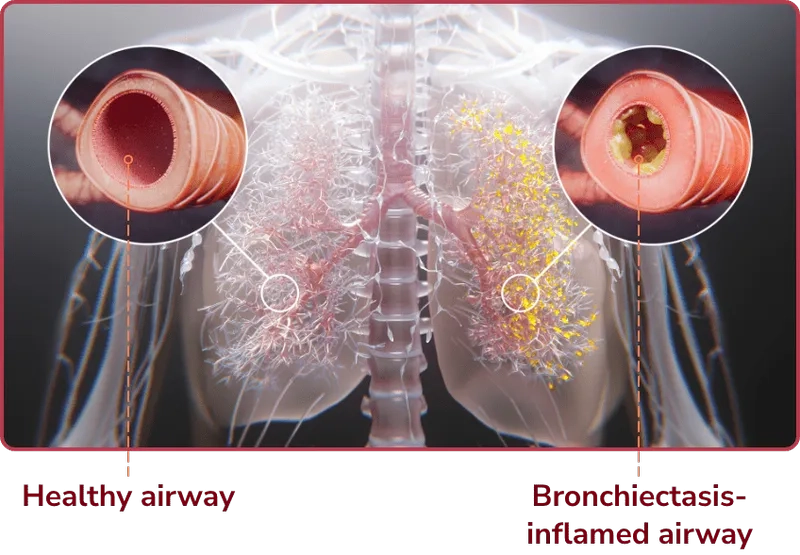

• Bronchiectasis is a disease where the lung's airways become permanently damaged and widened, making it difficult to clear mucus and leading to infections.

Diagram of lungs with Bronchiectasis